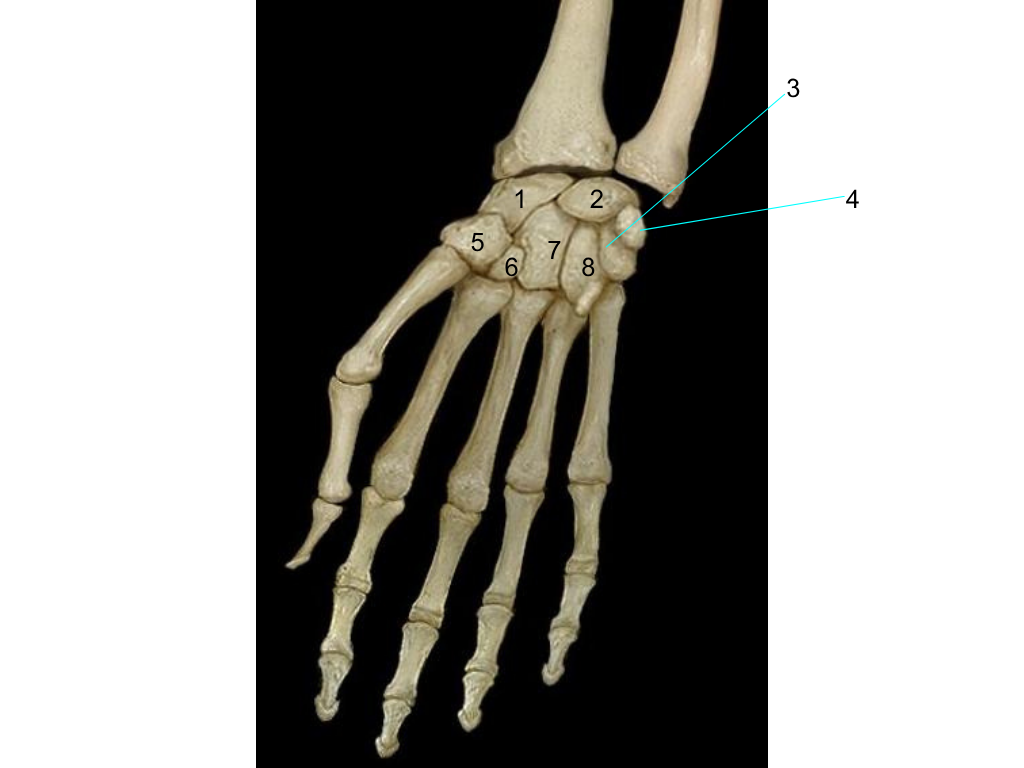

scaphoid

what is #1 pointing at?

lunate

what is #2 pointing at?

triquetrum

what is #3 pointing at?

quisiform

what is #4 pointing at?

trapezium

what is #5 pointing at?

trapezoid

what is #6 pointing at?

capitate

what is #7 pointing at?

hamate

what is #8 pointing at?